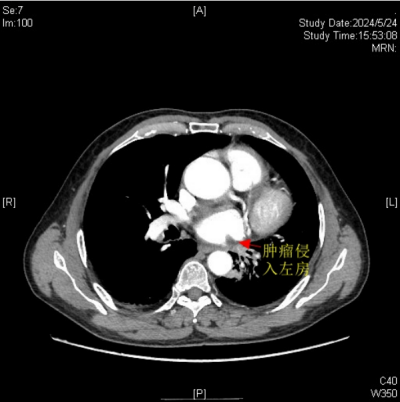

肿瘤侵入左心房

据悉,今年67岁的楚天海(化名)有长达40余年的吸烟史。因反复咳嗽、咯血等症状持续3个月之久,来到立博体育|实时赛事直播与比分|权威专家分析与体育竞猜平台 胸心外科门诊就诊。经全面检查与评估,诊断他患有左肺中央型鳞癌,且肿瘤有部分侵入左心房,情况凶险。

胸心外科主任、主任医师袁跃西表示,由于肿瘤侵入左心房,传统手术方式会因为手术视野受限、可能出现难以控制的大出血风险、肿瘤切除可能不彻底及术后恢复难度大等问题,如何确保患者安全并彻底切除肿瘤,成为了摆在医疗团队面前的难题。